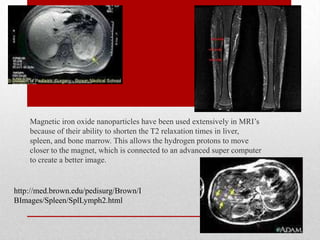

Magnetic iron oxide nanoparticles have been used extensively in MRI’s

because of their ability to shorten the T2 relaxation times in liver,

spleen, and bone marrow. This allows the hydrogen protons to move

closer to the magnet, which is connected to an advanced super computer

to create a better image.